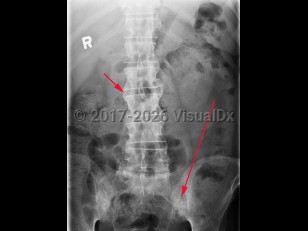

Abdominal aortic aneurysmAbdominal aortic aneurysm